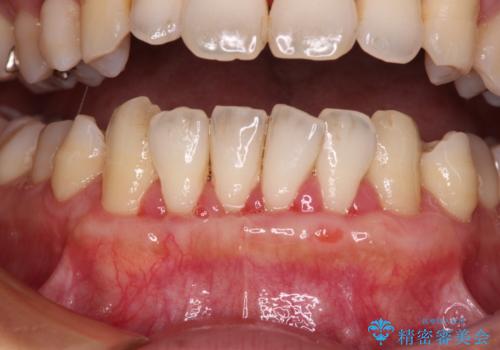

- 年々歯肉退縮が進行することを気にして来院された患者様です。

歯肉が菲薄であることが経年的な進行の原因であることが推察されたため、上顎からの結合組織移植術(CTG)により、歯根の被覆を行うとともに、歯肉の厚みを増すことで将来の退縮リスクを抑制することとしました。

上顎両側から歯肉を採取したたため、術後は痛みや出血で辛い思いをされましたが、1回の処置で満足のいく結果となりました。

根面被覆量も改善できましたが、歯肉の厚みが十分なものとなったことで、今後の歯肉退縮に歯止めをかけることができました。